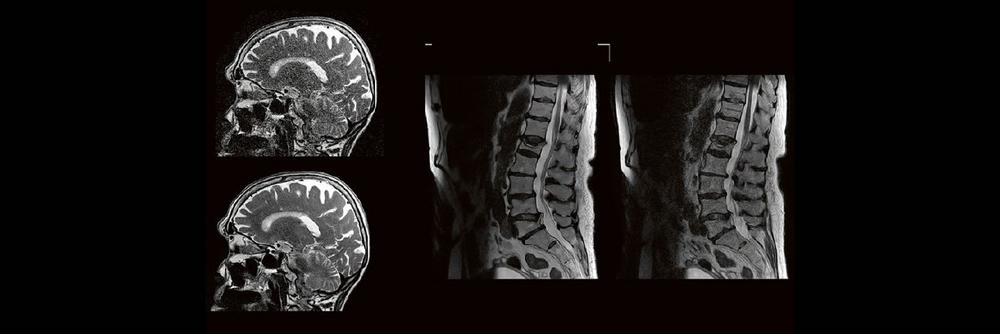

Professor Dr. med. Marc Brockmann WEITERENTWICKLUNGEN VON KOPF BIS FUSS BEIM VC Oberstarzt Dr. med. Stephan Waldeck DEEP-LEARNING-REKONSTRUKTION IN DER NEURORADIOLOGIE Die CT ist ein essentielles Routine-Verfahren in der Neuroradiologie. Bei steigender Bildqualität konnte die Röntgendosis mit neuen Technologien in der letzten Dekade deutlich gesenkt werden, was für die zielgerichtete und möglichst schonende Behandlung von

Professor Dr. med. Matthias PumbergerPD Dr. med. Torsten Diekhoff Die Dual-Energy-Computertomographie (DECT) hat für viele klinische Anwendungen bereits Einzug in die Praxis genommen. Für die Behandlung von Wirbelsäulenerkrankungen sind besonders die Darstellung von Knochenmarkveränderungen (z. B. bei osteoporotischen Frakturen) und der Bandscheibe (z. B. bei Bandscheibenvorfällen) interessant und werden intensiv beforscht. Hierdurch versprechen wir uns